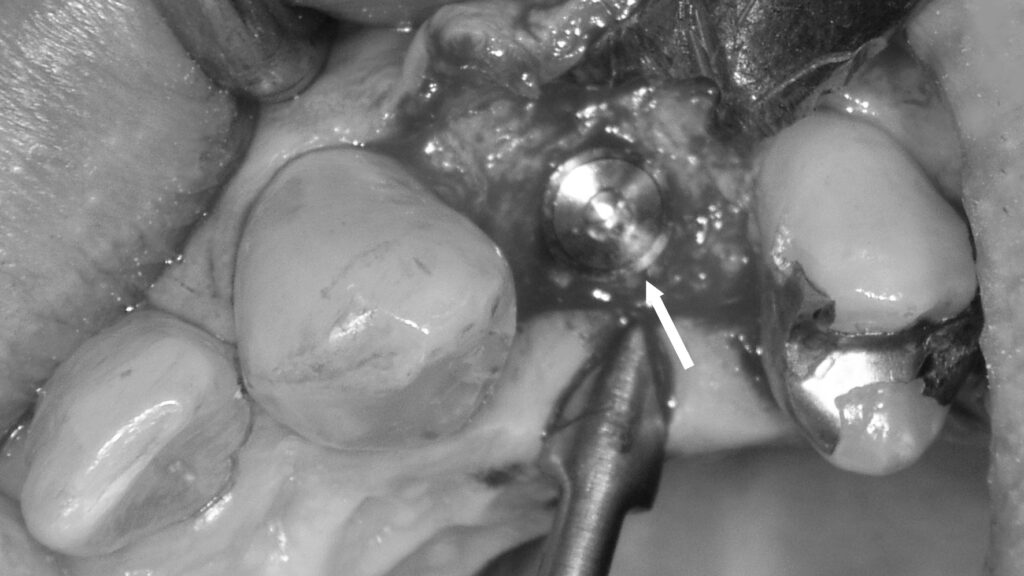

メタルコアによる支台築造とシェードテイキング

この画像は、前歯部の補綴治療中(被せ物作製前)の状態を示しています。赤い矢印で示された部分には、白金加金製のメタルコアが装着されています。以下に詳しく説明します。

🦷 写真の概要

- 赤い矢印の部分:白金加金のメタルコア

- 失活歯(神経を取った歯)の根管内に金属の支台(コア)が入っています。

- この金属は「白金加金」で、強度・適合性に優れ、長期的に安定した材料です。

- メタルコアは歯の根を補強し、その上にクラウン(被せ物)を装着するための土台になります。